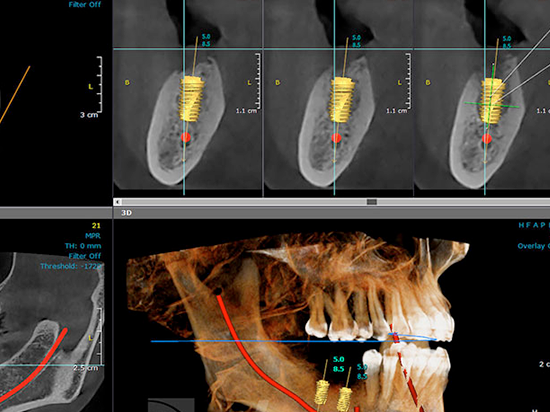

La endodoncia, es un procedimiento odontológico que consiste en prolongar la vida del diente en la boca cuando su pulpa está dañada.